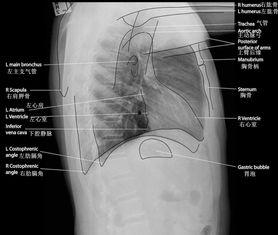

x线视频教学,顾名思义,就是通过视频的形式,将x线检查过程中的操作步骤、注意事项以及常见问题进行详细讲解。这种教学方式不仅可以让学习者直观地了解x线检查的全过程,还能在轻松愉快的氛围中掌握相关知识。

1. 直观易懂:相比于枯燥的文字描述,视频教学更能让你身临其境地感受到x线检查的过程,让你在短时间内掌握操作技巧。